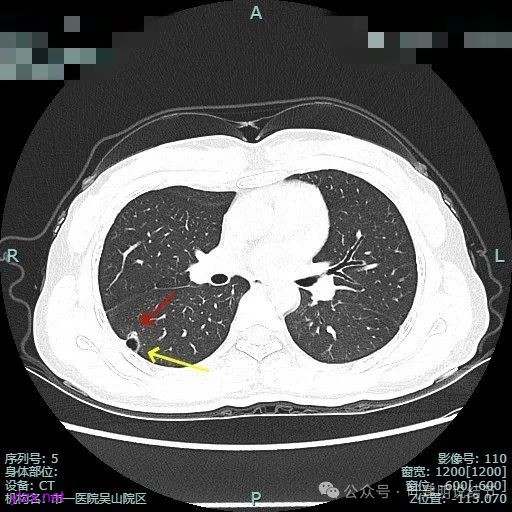

靶重建的影像上看,病灶的囊壁明显厚薄不均,有小血管进入,一侧的边似就是斜裂的样子。

囊壁有磨玻璃成分,边缘毛糙,有少许偏实性成分,仍有磨玻璃成分。

血管走向病灶,囊壁略不均。

此层见囊壁有较明显实性成分,血管进入明显。叶间裂侧平直。